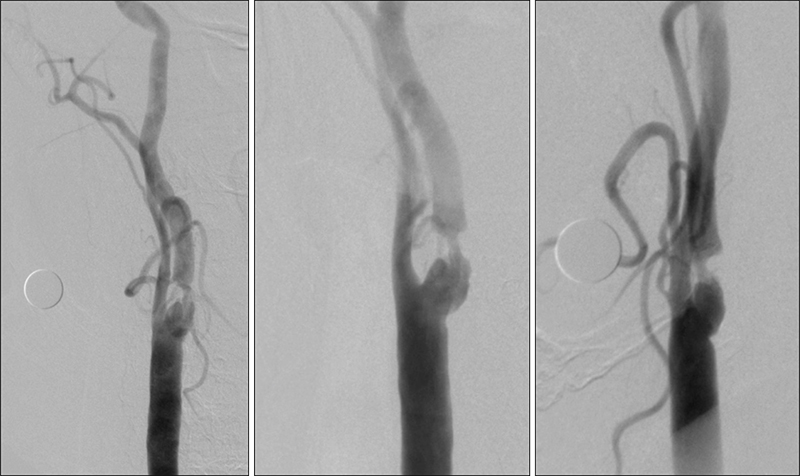

Εικόνα 1 και 2: Προσθιοπίσθια και πλάγια λήψη εγχύσεως στην αριστερή κοινή καρωτίδα. Εξεσημασμένη αθηρωματική στένωση (>95%) της εκφύσεως και του βολβού της αριστερής έσω καρωτίδος, με ελείμματα πληρώσεως (πρόσφατο θρομβωτικό υλικό). Η ροή υπεράνω της στενώσεως είναι ελαττωμένη και και καθυστερημένη.